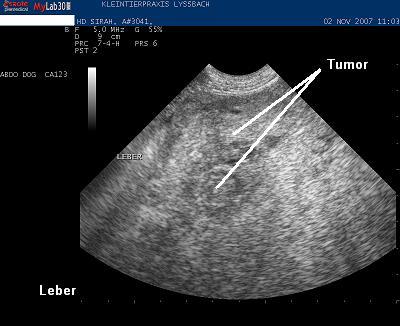

Die Untersuchung bestätigt, dass der Geschwulst von der Leber ausgeht. Die Leber ist weiträumig durchsetzt von grossen und kleinen Knoten von unterschiedlicher Echotextur und Echogenität. Dringender Verdacht eines Lebertumors (Leberkrebs).